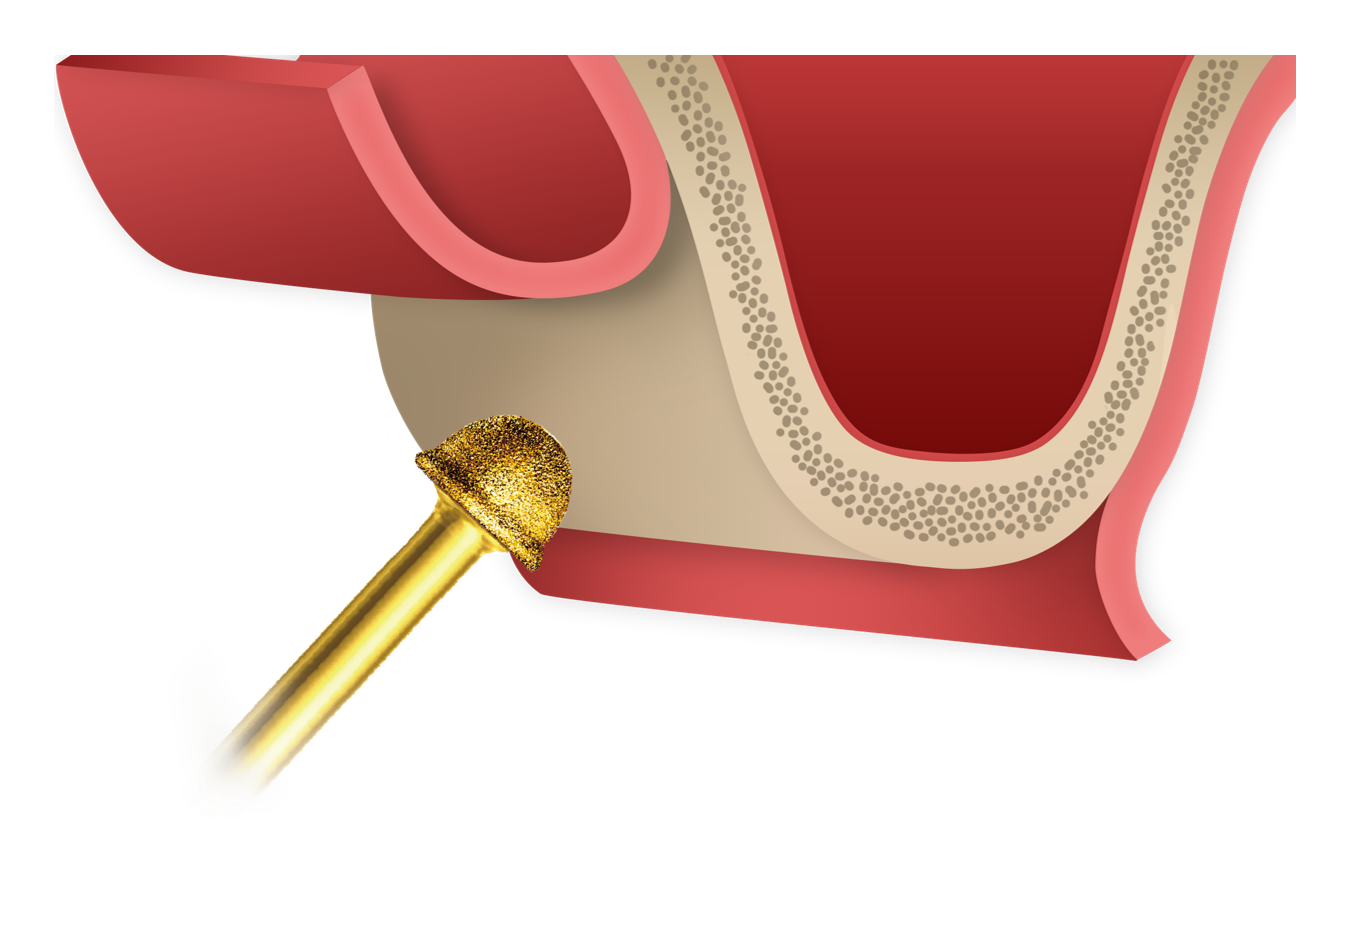

Thin-out Technique

Thin-out TechniqueControlled thinning of the lateral wall enables precise window formation and safe sinus membrane elevation.

Thin-out Technique

Thin-out Technique -